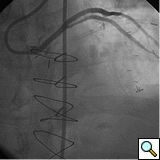

The most commonly used catheters for left heart catheterization and vein graft angiography can be seen in Figure 1 and Figure 4-13. Most of the vein grafts have horizontal take off and can be successfully engaged using a commonly used Judkins right number 4 (JR4) catheter. The JR4 catheter is the most commonly used catheter for the engagement of the right coronary ostium with horizontal take off. However, many vein grafts have unusual take off requiring different catheters. Many right coronary vein grafts have steep inferior take off making the ostial engagement with JR4 difficult or impossible (Figure 10). In such a scenario, a multipurpose catheter which has a shallow angulation is the best choice (Figure 11). The second major challenge in engaging vein graft ostia, particularly vein grafts supplying the left coronary arteries, is the shape of the aorta. A large aorta can make it very difficult for the JR4 catheter to reach the ostial vein grafts. In such a situation, Amplatz (AR) right and left (AL) catheters can be very helpful to reach the vein graft ostia. Amplatz catheters have a larger primary curve and have been used successfully in unusual superior take off of left coronary arteries or vein grafts and in large aorta. Amplatz catheters are available in different sizes (from smaller to larger curve: AR 1, AR2, AL2, AL2 and AL3). Occasionally, a very superior take off of a vein graft requires specially designed bypass graft catheters. Amplatz catheters are also extremely helpful in engaging native right coronary ostium with anterior take off.

PCI of the vein and arterial grafts have unique challenges. For any PCI, guide support is very important for successful balloon and stent delivery. In a tortuous vein graft with a steep angle, advancement of a stent can be very difficult and challenging. Therefore, it is important to choose the best available catheter before starting PCI. Similar to the right coronary angiography, a JR4 guide catheter is most commonly used in this setting. However, Amplatz guide catheters for left vein grafts and multipurpose catheters for right vein grafts are better choices in certain anatomy. In Figure 8 and Figure 10 two examples of poor guide support in two vein graft interventions can be seen. Initially, a JR4 guide was used for PCI of the vein graft supplying the left anterior descending artery (LAD) without any success. However, after changing the guide to an Amplatz left 2 guide catheter, we achieved excellent support without any difficulty in advancing two stents (Figure 9). In Figure 10, difficulty is illustrated in engaging the vein graft ostium supplying the right coronary artery with a JR4 catheter. This vein graft has a very steep inferior take off from the aorta. After changing the guide to a multipurpose catheter, we were able to deliver three stents successfully without any difficulties (Figure 11). Similar challenges exist in the treatment of the left IMA or right IMA. These arterial grafts can be extremely tortuous making stent delivery very difficult. It may be necessary to use short length stents for a better deliverability or stents with lowest profile. Usually, similar to the native coronary intervention, a 6 French guide is appropriate for the routine use.